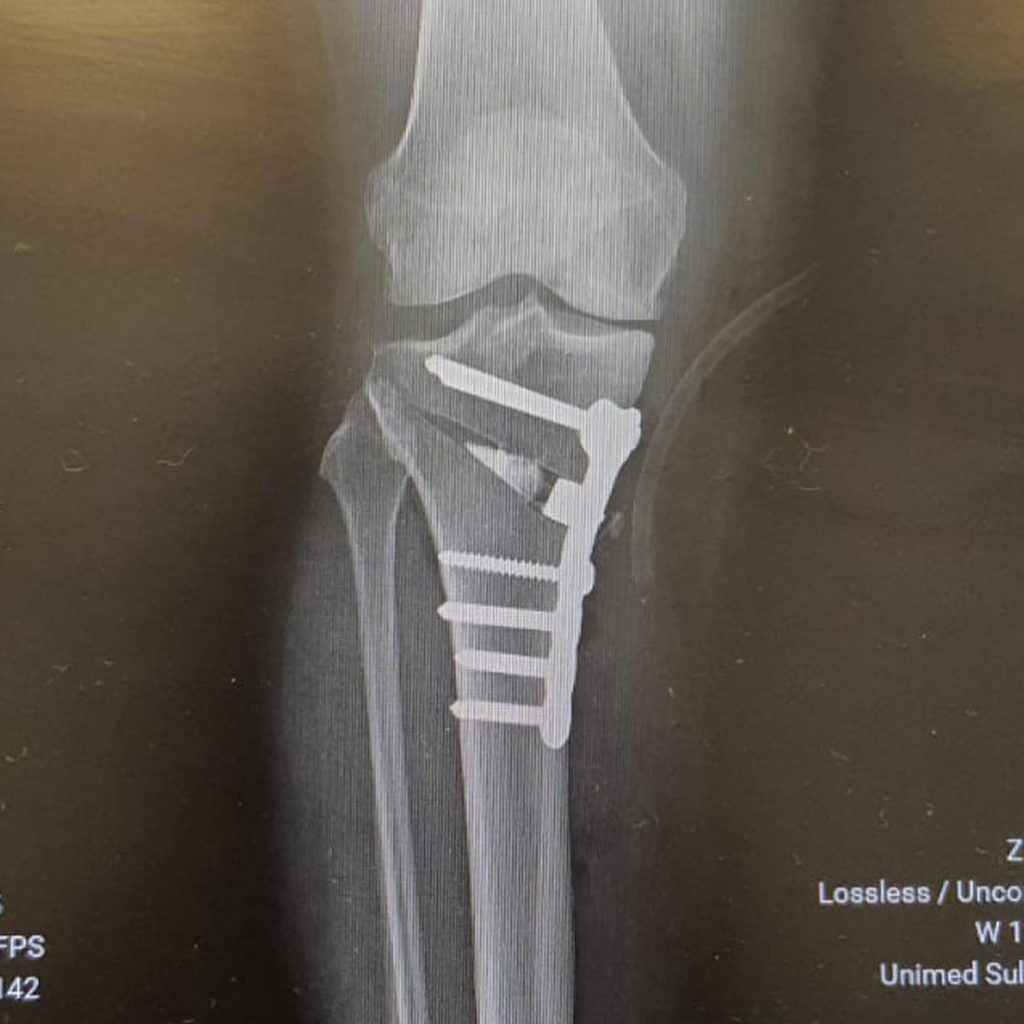

Essa paciente tinha a “perna cambota” nome popular para Deformidade em Varo além de uma artrose inicial.

Nosso especialista em Joelho Dr Danilo Lobo @daniloslobo realizou cirurgia Osteotomia Corretiva valgizante com placa, que é a correção do eixo da perna e colocação de placa.